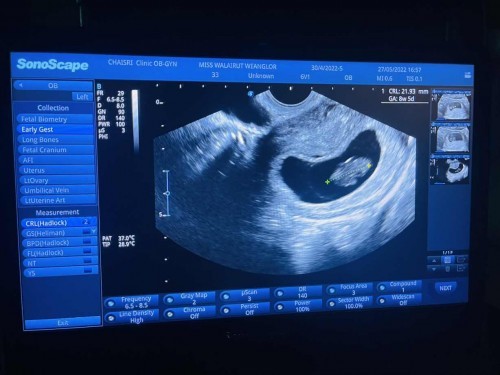

8w5dไปซาวดูคุณหมอบอกน้องโตแต่ยังไม่ได้ยินเสียงหัวใจ เป็นกังวลมากค่ะ ว่าปกติไหมแบบนี้